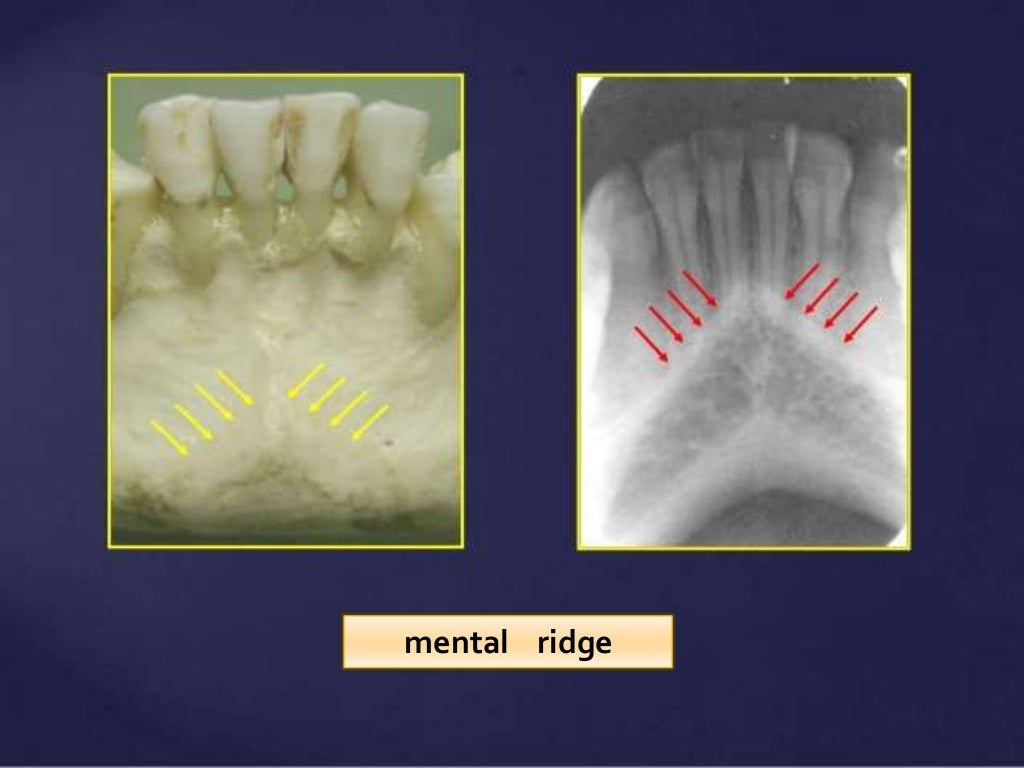

Intra Oral radiographic anatomical landmarks Landmarks Radiology this article deals with identification and descriptions of intraoral and extraoral anatomy of the dental and maxillofacial structures. the department of radiology, skh offers all diagnostic and interventional radiology investigations along with nuclear. interventional radiology is a subspecialty of radiology that involves the performance of minimally invasive procedures guided by. many vertebral levels are associated with. Landmarks Radiology.